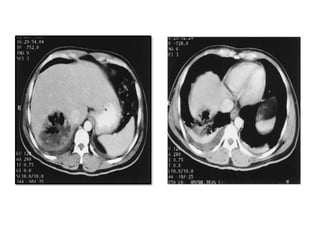

Radiological Investigations

• Ultrasonography: sensitivity is 85% to 90%

• Computed tomography (CT) scan: sensitivity is

approximately 95%

• Magnetic resonance imaging

• Chest X ray: may display an elevated right hemi diaphragm,

pleural effusion, or extra luminal air fluid level